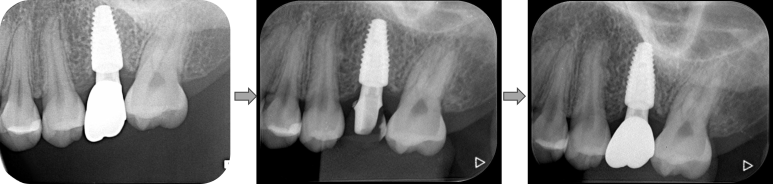

환자분은 과거 교정 치료를 받으신 적이 있으셨고,

좌측 위 어금니 부위(#27)는 앞으로 기울어진 상태였습니다.

그 앞쪽 치아(#26)는 임플란트로 식립된 상태였고,

#26과 #27 사이에 음식물 끼임과 잇몸 불편감을 호소하며 내원하셨습니다.

🔎 초기 진단 결과

- #26 임플란트 보철물의 뒷면이 비정상적으로 눌려있음

- Marginal ridge 높이 차이로 인해 치아 사이 압박 발생

- 보철물과 잇몸 사이에 자극 → 만성 염증 가능성